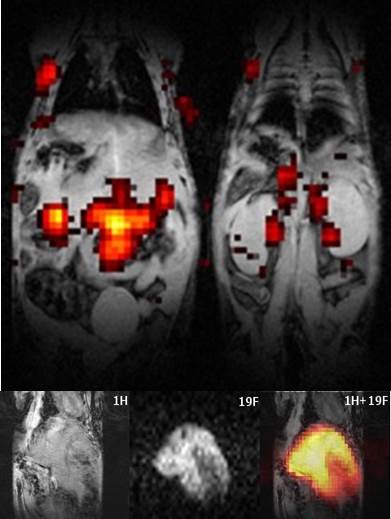

Mesoporous silica nanoparticles are highly promising drug carriers due to their inherent biodegradability, low toxicity, high surface area and pore volumes. Furthermore, different imaging modalities can be grafted onto the particles enabling parallel imaging with clinically relevant imaging techniques, including MRI and PET. Our current research in this are concentrate on the